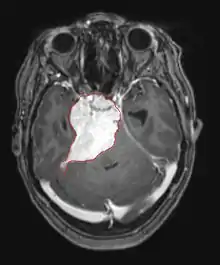

La tomodensitométrie (TDM) et L'imagerie par résonance magnétique (IRM) peuvent détecter efficacement une néoplasie dans le cerveau. L'IRM est plus sensible que la TDM pour identifier les lésions, mais présente des contre- indications pour les patients porteurs de stimulateurs cardiaques, de prothèses incompatibles, de clips métalliques et contre-indications. La TDM reste la méthode de choix pour détecter les calcifications au sein des lésions ou les érosions osseuses de la calotte ou de base du crâne. L'utilisation d' agents de contraste, iodés dans le cas du scanner et paramagnétiques (gadolinium) dans le cas de l'IRM, permet l'acquisition d'informations sur la vascularisation et l'intégrité de la barrière hémato-encéphalique, une meilleure définition de la tumeur tumorale par rapport à l' œdème environnant et à la génération d' hypothèses sur le degré de malignité. L'examen radiologique permet également d'évaluer les effets mécaniques et les modifications importantes des structures cérébrales résultant de la tumeur, telles que l' hydrocéphalie et les hernies, dont les effets peuvent être fatals. Enfin, en préparation à la chirurgie, ce diagnostic peut être utilisé pour déterminer la localisation de la lésion ou l'infiltration de la tumeur dans des zones vitales du cerveau. À cette fin, l'IRM est plus efficace que la tomodensitométrie car elle peut fournir des images en trois dimensions.

Sur-L'IRM montre une tumeur intracrânienne comme une lésion massive qui peut devenir plus luminescente après utilisation du produit de contraste. Cependant, il y a toujours une anomalie de signal dans -L'imagerie par résonance magnétique, qui indique la présence d'une néoplasie ou d'un œdème vasogénique. Habituellement, une luminescence accrue (amélioration du contraste) indique une tumeur d'un grade supérieur de malignité. Un anneau de contraste est caractéristique du glioblastome, avec la partie luminescente correspondant à la partie vitale de la tumeur maligne, et la plus foncée - zone hypointense correspondant à une nécrose tissulaire.

En règle générale, les patients atteints d'astrocytome anaplasique présentent des crises d'épilepsie, des déficits neurologiques focaux, des maux de tête et des changements de personnalité. L'âge moyen des patients est de 45 ans. L'imagerie par résonance magnétique montre généralement une lésion massive avec un signal de contraste accru, qui peut aussi être plus faible. Le diagnostic repose sur l'examen histologique de la lésion par biopsie ou résection chirurgicale.

Les patients souffrent d'une variété de symptômes caractéristiques d'une lésion massive focale ou multifocale. L'IRM montre généralement des tumeurs avec un rehaussement de contraste homogène au sein de la substance blanche périventriculaire profonde. La multifocalité et le rehaussement inhomogène sont typiques des patients dont le système immunitaire est affaibli. L'analyse du lymphome du SNC est extrêmement importante dans le diagnostic différentiel de la néoplasie cérébrale. Il est à noter que l'administration de corticoïdes peut entraîner la disparition complète du rehaussement, rendant difficile le diagnostic des lésions. Par conséquent, si un lymphome du SNC doit être pris en compte dans le diagnostic différentiel, les corticoïdes doivent être évités à moins que l'effet de masse ne provoque un problème grave et immédiat chez le patient.